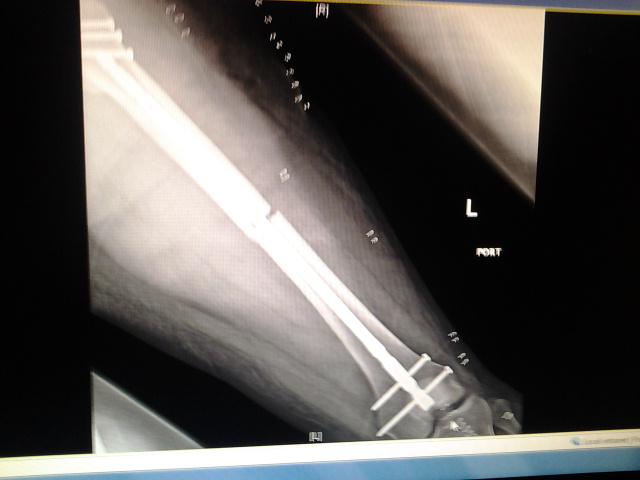

So... To start, I had a motorcycle accident and broke my leg in two places. They had to insert a rod and a bunch of screws in. But I think I had nerve damage. How I know? Well the outside of both my legs to the small toes are numb. Not totally, I have feeling. But they're numb.

I had the accident on 4-7-14. Been non-weight bearing on my left leg since.

Attachment:

2014-04-10 08.08.20.jpg

2014-04-10 08.08.20.jpg [ 84.72 KiB | Viewed 5366 times ]

2014-04-10 08.07.56.jpg

2014-04-10 08.07.56.jpg [ 91.21 KiB | Viewed 5366 times ]

Just don't ask me how my bike fared :/